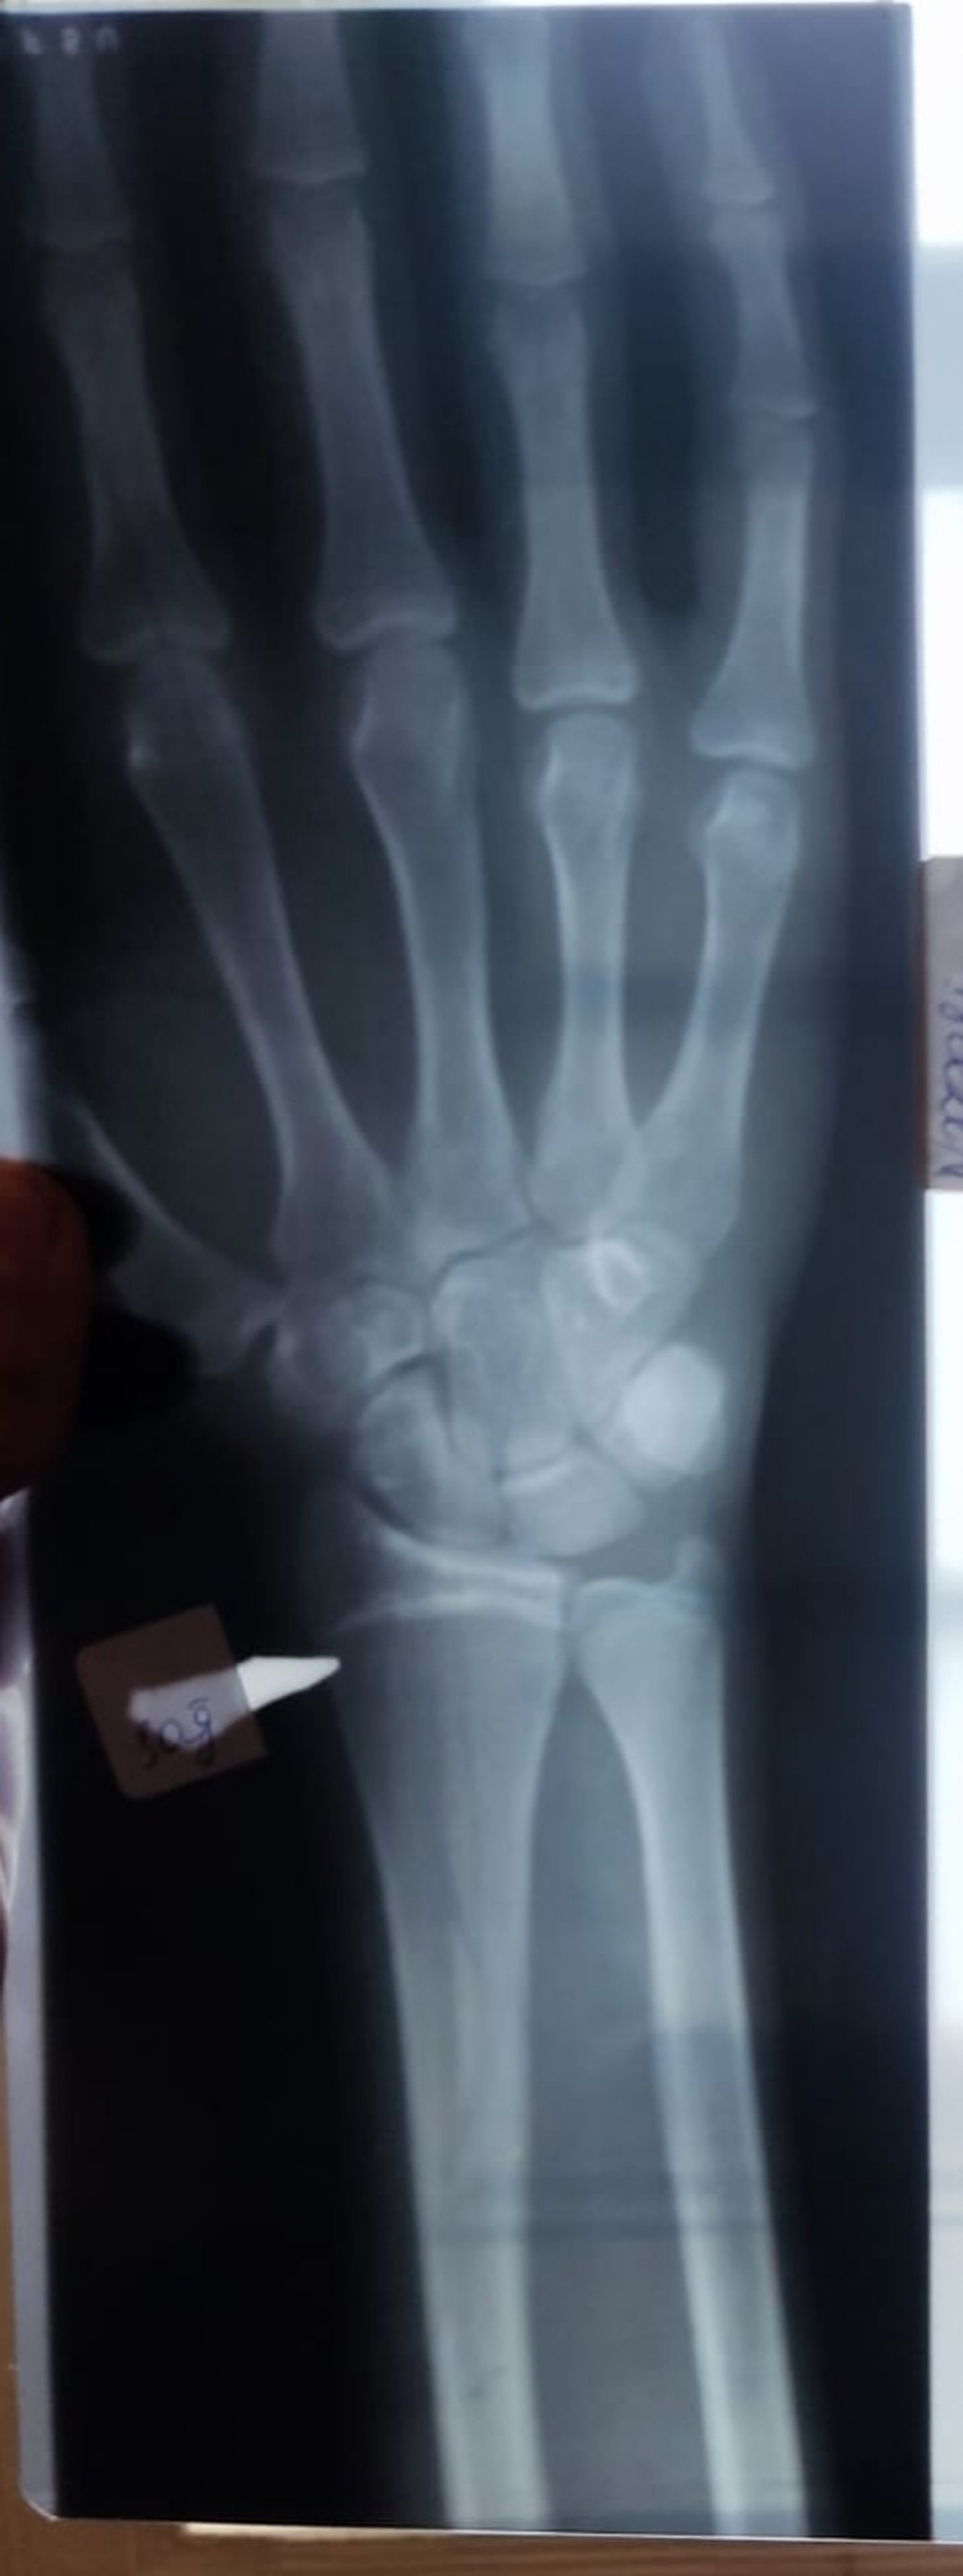

18 den sonra boy uzanırmı Epifiz plaklarim kapanmaya yaklasmış bir kaç sm daha uzaya bilsem iyi olur?